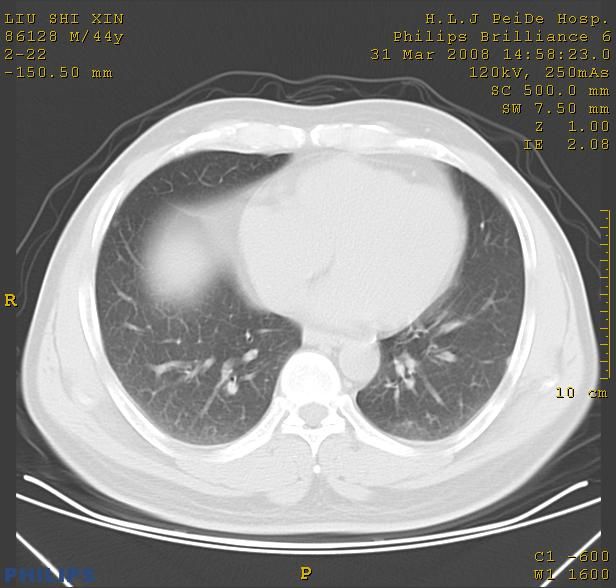

标题: CT13096:请分析胸膜下结节的影像基础是什么 有病理结果 [打印本页]

标题: CT13096:请分析胸膜下结节的影像基础是什么 有病理结果

瘢痕挛缩,胸膜牵拉,血管纠集扭曲,上叶前段支气管显示欠清,周围散在斑片影,以纵隔旁肺癌可能性大。请穿刺检查。

中心型肺癌并阻塞性肺炎、两肺及胸膜多发转移。

结节灶与血管末梢相通象转移灶;小三角状尖部有纤维索是胸膜拉扯征;纵隔旁大片实性影有点状钙化;周围有名显纤维瘢痕征可考虑瘢痕癌

典型的肺癌胸膜转移!没啥鉴别诊断!

本病例有病理结果是,鳞状上皮癌,胸膜下结节影病现诊断的肿大淋巴结,谢谢大家分析,请问胸膜下结节是肿大淋巴结怎么解释